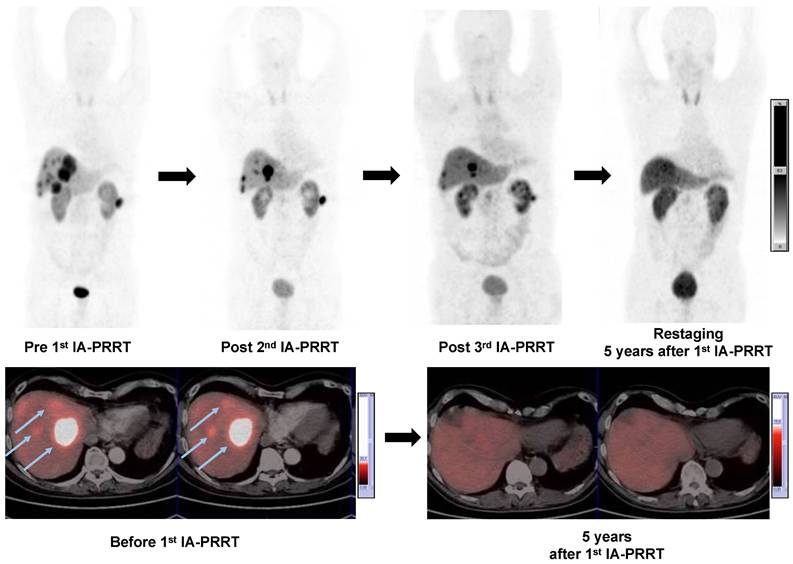

Figure 4

A 57-y-old man with well-differentiated, nonfunctioning metastatic pancreatic NEN. Maximum-intensity-projection (MIP) (top-left, Pre 1st IA-PRRT) images from 68Ga-SSTR PET/CT showed SSTR expression in liver metastases (arrows) and lymph nodes metastases with SUVmax of 41.4. Patient was treated with 3 cycles of 90Y-DOTATATE IA-PRRT with cumulative administered radioactivity of 12.7 GBq. After the 2nd IA-PRRT and 3rd IA-PRRT, 68Ga-SSTR PET/CT showed significant regression of the liver and paracolic lymph node metastases (PR). MIP images from restaging 68Ga-SSTR PET/CT 5 years after 1st IA-PRRT showed complete remission of the lesions. No adverse effects were observed during and after the treatment with long-term follow-up.

Theranostics Image